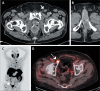

Objective: To investigate clinical, pathology, and imaging findings associated with inguinal lymph node (LN) metastases in patients with prostate cancer (PCa).

Materials and methods: This was a retrospective single-center study of patients with PCa who underwent imaging and inguinal LN biopsy between 2000 and 2023. We assessed the following aspects on multimodality imaging: inguinal LN morphology; extrainguinal lymphadenopathy; the extent of primary and recurrent tumors; and non-nodal metastases. Imaging, clinical, and pathology features were compared between patients with and without metastatic inguinal LNs.

Results: We evaluated 79 patients, of whom 38 (48.1%) had pathology-proven inguinal LN metastasis. Certain imaging aspects- short-axis diameter, prostate-specific membrane antigen uptake on positron-emission tomography, membranous urethra involvement by the tumor, extra-inguinal lymphadenopathy, and distant metastases-were associated with pathology-proven inguinal LN metastases (p < 0.01 for all). Associations with long-axis diameter, fatty hilum, laterality, and uptake of other tracers on positronemission tomography were not significant (p = 0.09-1.00). The patients with metastatic inguinal LNs had higher prostate-specific antigen levels and more commonly had castration-resistant PCa (p < 0.01), whereas age, histological grade, and treatment type were not significant factors (p = 0.07-0.37). None of the patients had inguinal LN metastasis in the absence of locally advanced disease with membranous urethra involvement or distant metastasis.

Conclusion: Several imaging, clinical, and pathology features are associated with inguinal LN metastases in patients with PCa. Isolated metastasis to inguinal LNs is extremely rare and unlikely to occur in the absence of high-risk imaging, clinical, or pathology features.